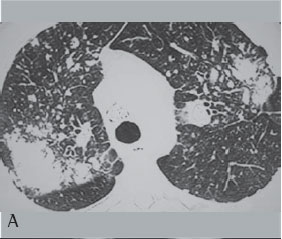

Dos 75 pacientes portadores de FMP, 44 realizaram TCAR de tórax. Quanto às características das massas analisadas pela TCAR de tórax verificou-se que 88,6% predominaram nos terços superiores e eram posteriores. Escavações foram observadas em 18,18% das massas, broncograma aéreo em 70,4% e calcificação no interior das mesmas em 63,6% delas. Enfisema ao redor das massas foi observado em 72,7% e calcificação linfonodal em 81,8% dos casos (Figuras 3A e 3B).

Neste estudo, na TCAR de tórax as grandes opacidades predominaram nos terços superiores e posteriores dos pulmões (88,6%). Broncogramas aéreos e calcificações no interior das massas ocorreram em mais da metade dos pacientes. Linfonodos hilares e mediastinais calcificados foram observados em 81% dos casos, sendo 25% do tipo casca de ovo. Apenas 8 casos apresentaram escavação no interior das massas, sendo que 6 deles apresentavam tuberculose associada.

Alguns autores(20) descreveram calcificações esparsas no interior das massas da FMP decorrente da silicose, e outros(21) relataram calcificação linfonodal em 26 de 49 casos de silicose estudados, com 12,2% do tipo casca de ovo, sendo que esta manifestação radiológica foi muito mais freqüente na silicose complicada do que na nodular simples.